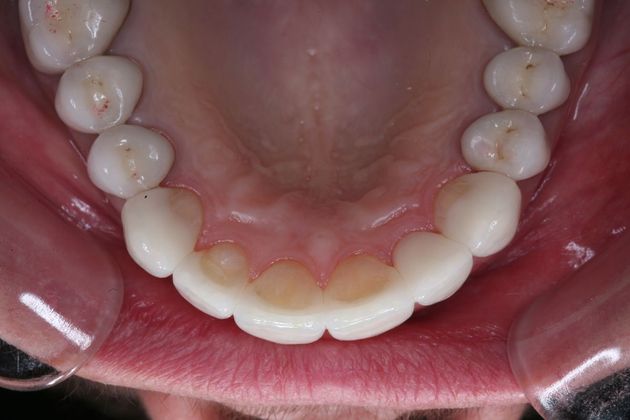

Procedures; TMJ CAT scan, TMJ deprogramming, whitening, sedation dentistry, reconstruction of all the back and upper front teeth with porcelain crowns, bite guard therapy. This foster care provider wanted to be free of the pain in her jaw joints. She had a lifelong history of grinding, many of her back teeth were breaking down and her bite was off. Her treatment was performed in sections to spread out the cost. She and her husband were so pleased with the result!